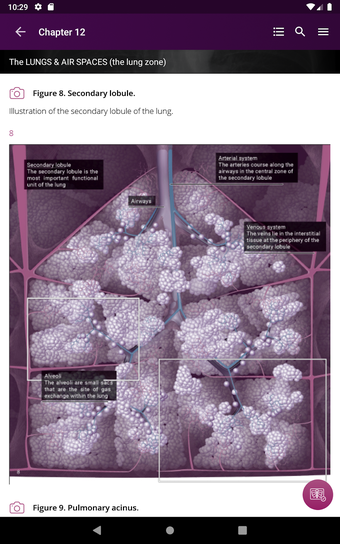

Radioloji'yi Keşfet: Göğüs Röntgeni Yorumlama, göğüs röntgeninin yorumlanmasının anlaşılmasını artırmak için tasarlanmış bir eğitim uygulamasıdır ve doktorlar, tıp öğrencileri ve radyologlar tarafından kullanılması amaçlanmaktadır. Uygulama, en küçük detayları görüntülemek için yakınlaştırılabilecek yüksek kaliteli görüntüler ve her bulgunun önemini anlamanıza yardımcı olacak bir sesli yorum içerir.

Uygulamanın amacı, kullanıcıların farklı x-ışını bulgularını ve bunların bir hastalığın teşhisinde nasıl kullanılabileceğini daha iyi anlamalarına yardımcı olmaktır. Uygulama, göğüs röntgeni yorumlaması için gerekli çeşitli yapı taşlarını kapsayan 5 bölüme ayrılmıştır.